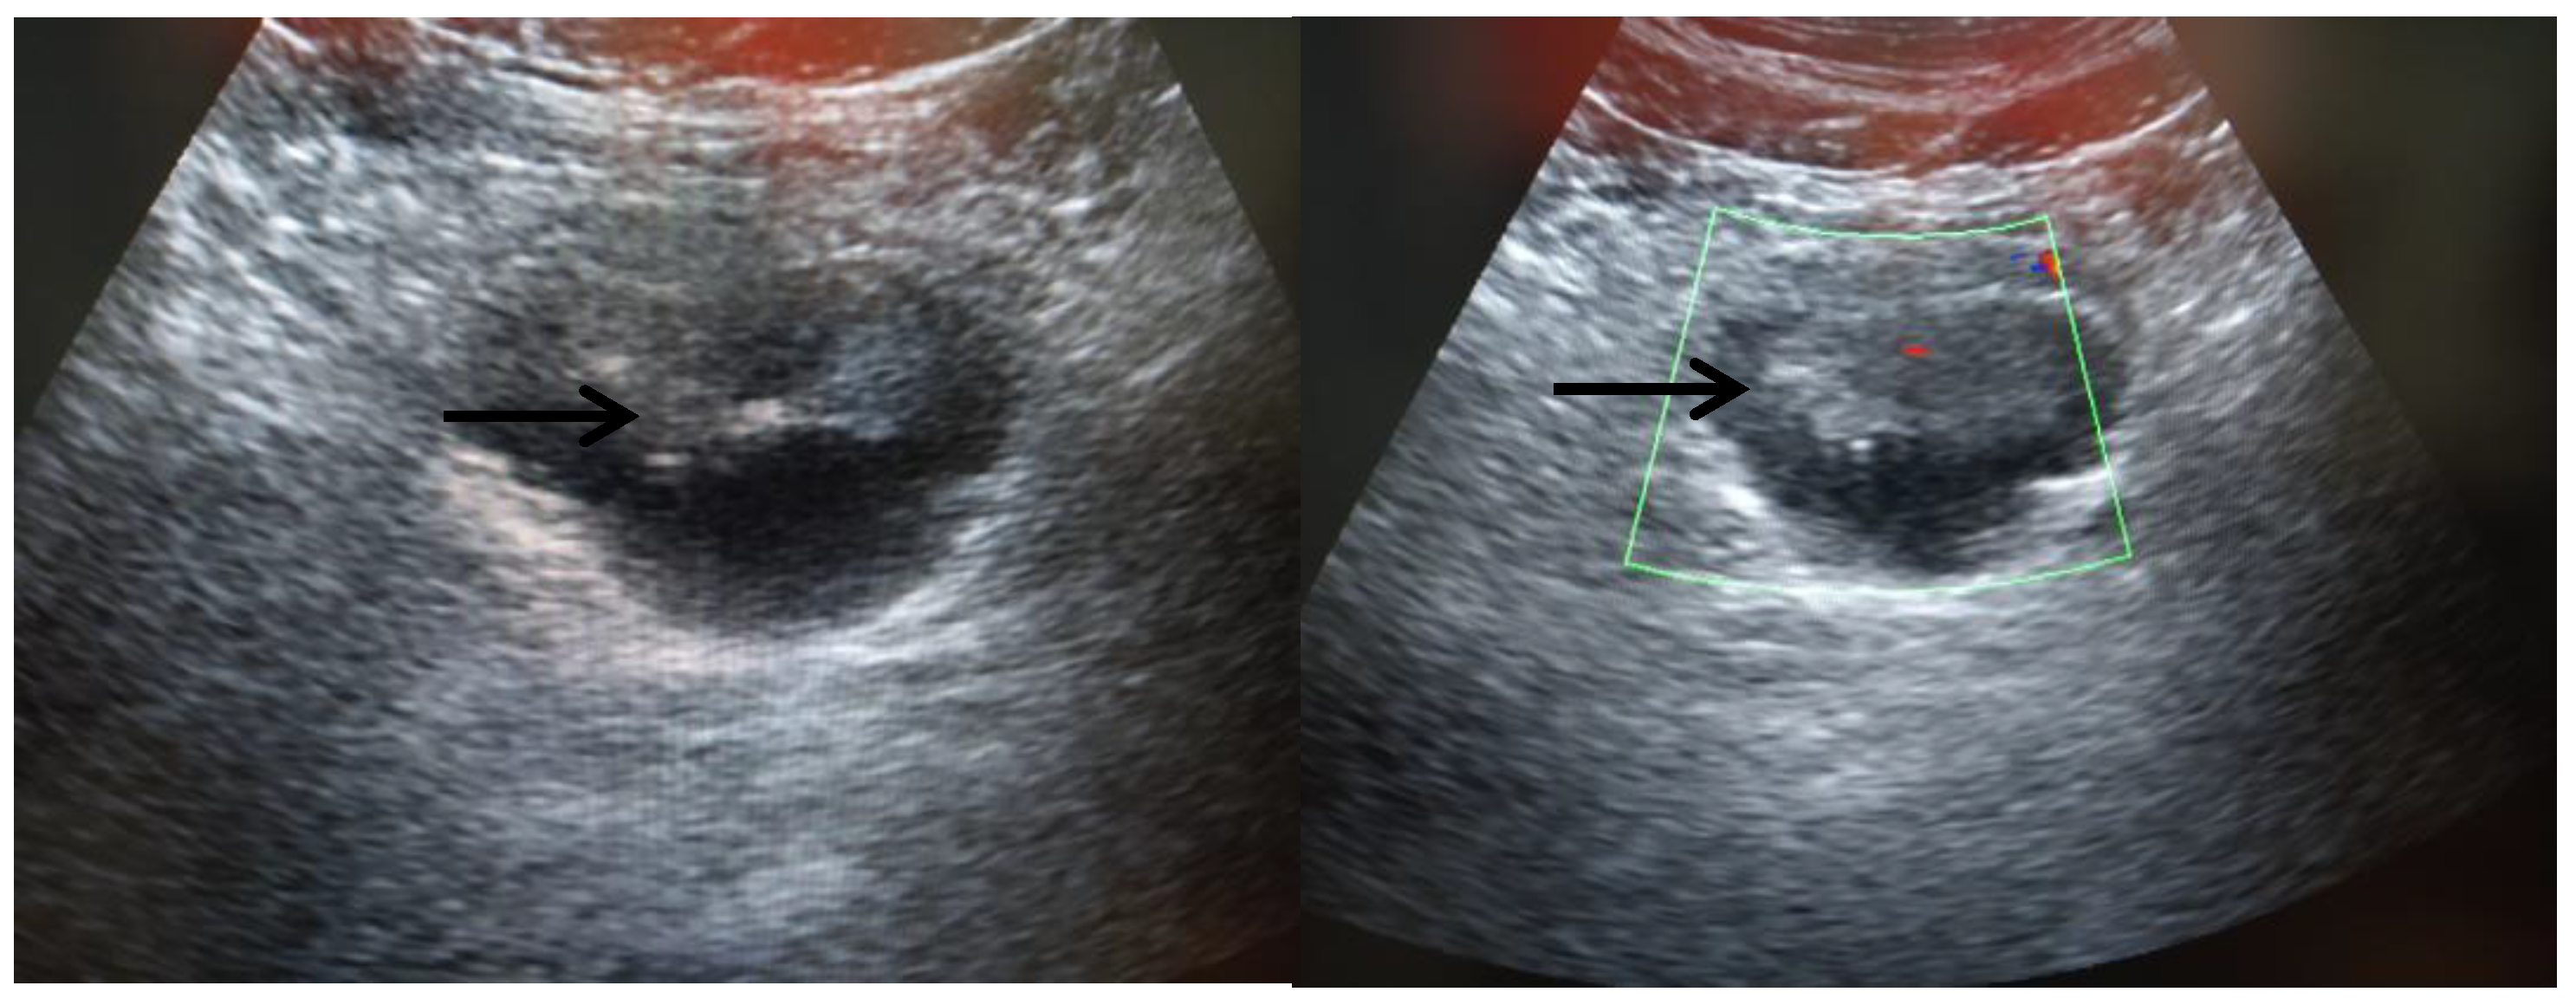

- ✓ Estudios imagenológicos: